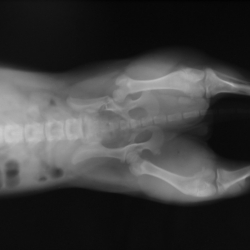

Fotogalerie